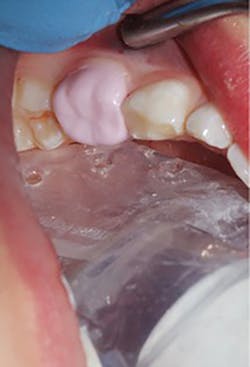

Cementation was then achieved as follows: Once satisfied with fit and occlusion, the prepared tooth was washed and dried but not desiccated. The NuSmile zirconia crown to be cemented was filled with cement (BioCem; NuSmile). Working time was approximately 60 seconds. The crown was set into the correct position. BioCem was photo cured with a tack cure of 10 seconds to the facial and 10 seconds to the palatal aspect. The cement was then cleaned interproximally using floss. Once all cement was removed, a final photo cure of 10 seconds to the facial and palatal was applied. One-month postoperative occlusal view and occlusion are pictured in Figures 4a and 4b.

Figures 4a and 4b: Final restoration